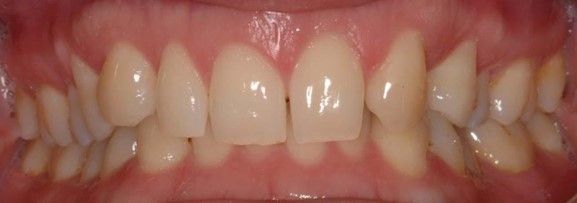

Se presenta un paciente varón de 34 años de edad, no fumador y sin antecedentes médico-quirúrgicos de interés (ASA I), que acudió a la consulta demandando una mejora en la estética de su sonrisa.

El paciente presentaba una agenesia congénita en el incisivo lateral superior izquierdo que había sido tratada previamente con ortodoncia para cerrar dicho espacio.

Tras el examen intraoral del paciente y el estudio radiográfico, se plantea la opción de tratamiento de abrir nuevamente el espacio mediante ortodoncia para rehabilitar la ausencia con un implante de circona, asegurando la estética que demandaba el paciente.